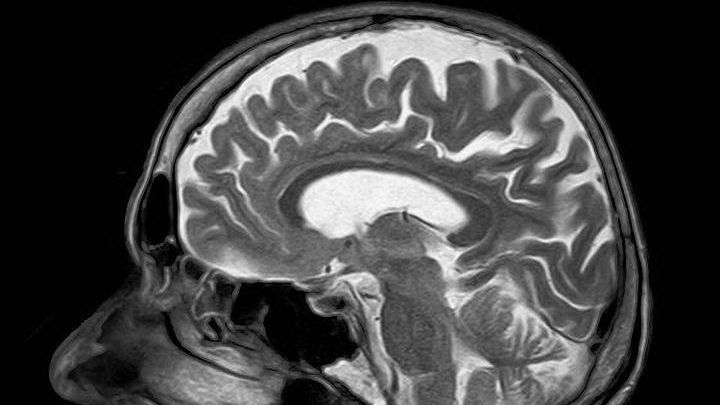

На пресс-конференции выступила мама первого ребенка, получившего лечение в Центре протонной терапии МИБС, — Екатерина Дрелинг. Она рассказала, что лечение проводилось на бюджетные средства, и ее сын во время лечения вел себя как обычно. У него был нормальный аппетит, никаких побочных эффектов не наблюдалось — не выпадали волосы, не разрушались зубы. Опухоль мозга не уменьшилась, но она перестала расти.

Напомним, что протонная терапия — один из самых современных способов лечения онкологических заболеваний. Первый в России клинический центр протонной терапии МИБС открылся в сентябре 2017 года. Сообщалось, что при полной загруженности центра лечение могут получить до 800 человек в год.